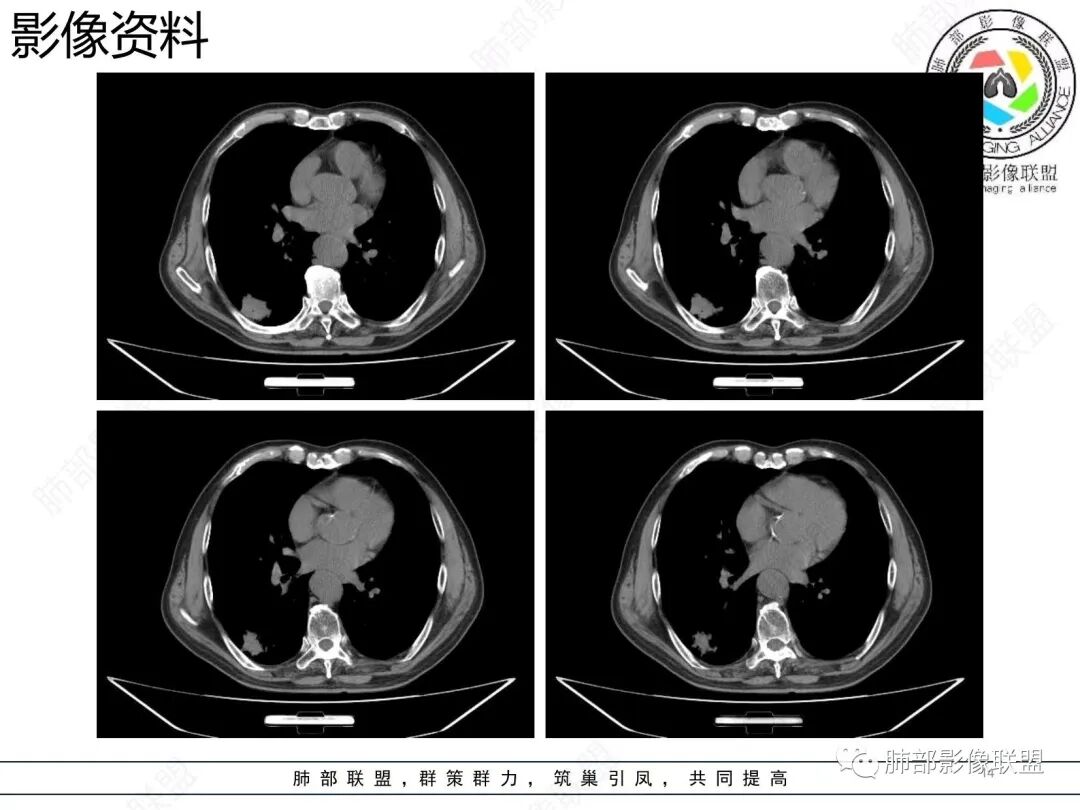

老年男性 右肺下叶胸膜下见一团状实性病灶+边缘磨玻璃,边缘形态不规则,,局部有平直,长轴平行于胸膜面,整体收缩力偏弱,邻近胸膜面轻度增厚,纵隔窗显示病灶内可见支气管充气,考虑炎性肉芽肿,隐球菌可能,鉴别黏液腺癌。

上面这些征象存在炎性病变可能,我先考虑炎性病变——隐球,这样的血管弯在肺隐球菌病里也出现过。腺癌尤其是粘液腺癌也不敢排除。建议完善血隐球菌荚膜抗原、经皮肺穿刺活检等检查。

增强,粘液腺癌的强化,和隐球菌的强化相差还是很大的

结节型粘液腺癌,具有血管弯,支气管截断,磨玻璃边界清楚等恶性征象,同时磨玻璃内部较糊,似清非清,不符合普通腺癌附壁生长特点,更像局限的粘液成分。收缩力不强,胸膜局部微积液,内部小空洞(考虑局部粘液排除形成),所以考虑结节型粘液腺癌。

1.结节型肺粘液腺癌以中老年女性多见,单发,发病部位常位于两下肺胸膜下(肺外周带)。                2.多数病灶具备典型恶性肿瘤征象,但是不典型者仍不少见。可有分叶和棘状突起,但较少出现典型毛刺征。强化程度不如一般的腺癌病灶那么显著。          3.病灶常呈圆形或不规则形,实性结节略多于混合磨玻璃结节,少见于纯磨玻璃结节;或囊实性结节影或肿块,密度混杂,部分可出现钙化;病灶边界可清楚,也可模糊,须与炎性结节鉴别;周围可有类圆形磨玻璃密度卫星灶;表现为实性结节病灶,收缩力可能表现不明显,较少胸膜凹陷或血管集聚,须与良性结节鉴别。                                                     4.原发性肺粘液腺癌侵袭力相对较低,发展慢;病灶较少破坏支气管及血管,可表现为血管造影征及空气支气管征。较少胸膜侵犯,也较少肺门纵隔淋巴结转移。

1.病理基础:肺原发性粘液腺癌的肿瘤细胞产生大量粘液,聚集于细胞内,破入细胞间隙甚至肺泡、末梢细支气管,致使病灶密度增高呈混合磨玻璃或实性结节。                                                         2.粘液的直接扩散和漂移,致使病灶边界模糊和病灶呈多灶性生长。                                            3.粘液的重力效应致使病灶常位于胸膜下或叶间胸膜附近。                                                       4.病灶内气管、血管破坏不明显,可出现血管造影征及空气支气管征;也提示病灶侵袭力较低。           5.粘液的张力(占位效应)常可抵消病灶收缩力,致使病灶收缩力表现常较弱。